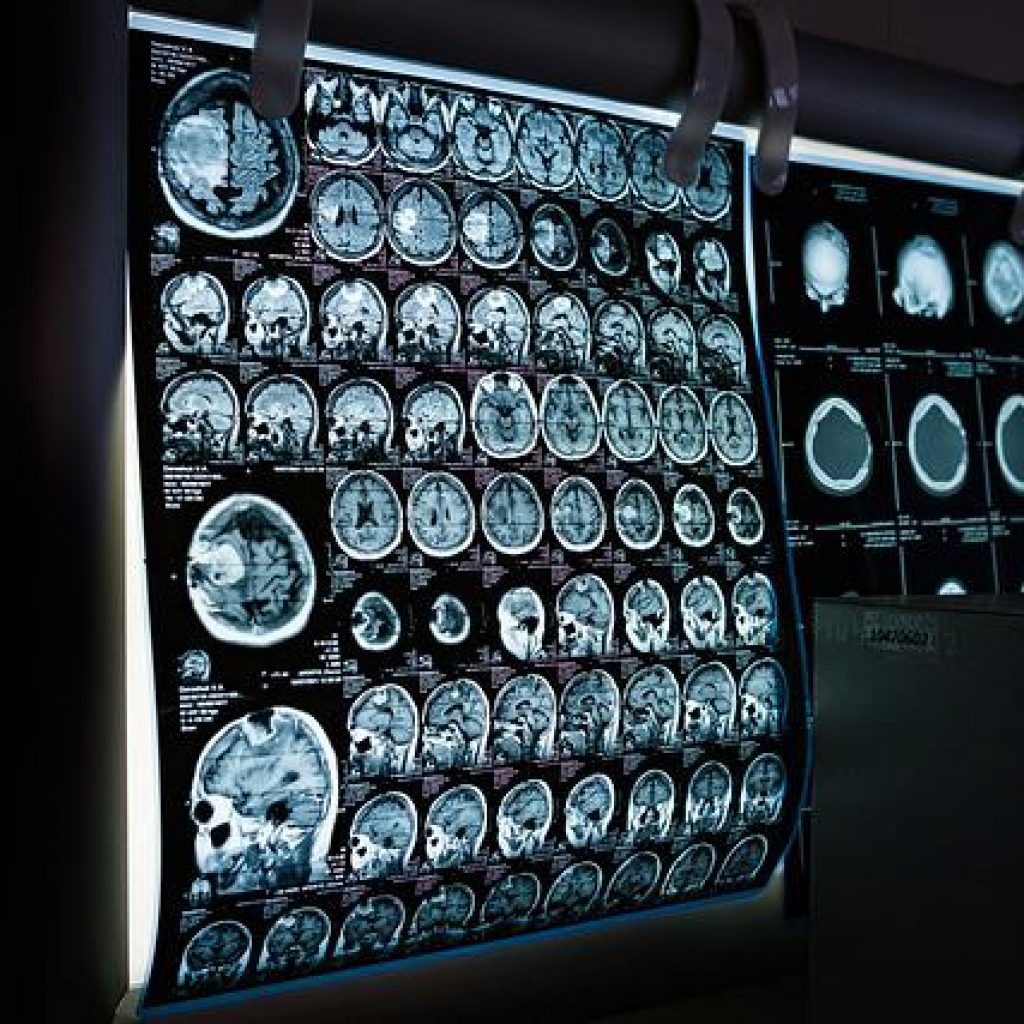

Military neck, also known as cadet’s neck, is a condition that is seen in young people who engage in sports or other physical activities that involve repetitive twisting of the neck. The condition is caused by a lesion on one of the vertebrae in the neck. The most common symptom of the military neck is pain in the neck that increases with activity. Other symptoms may include stiffness and difficulty turning the head. Diagnosis of the military neck is made based on history and physical examination. X-rays and magnetic resonance imaging (MRI) are typically used to assess the lesion. Treatment for military neck depends on the severity of the condition and may include rest, ice, compression, and elevation (RICE), physical therapy, and surgery.